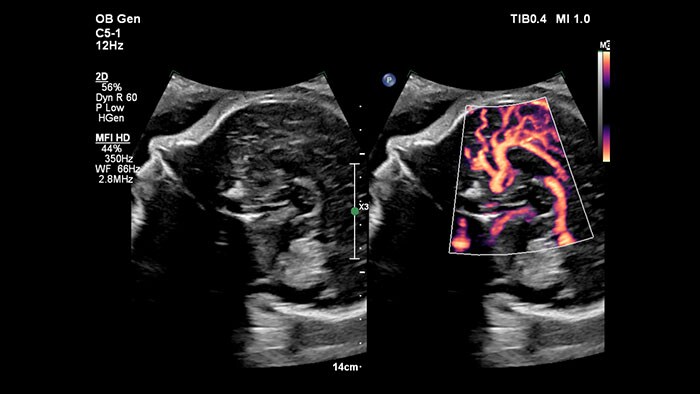

MFI HD